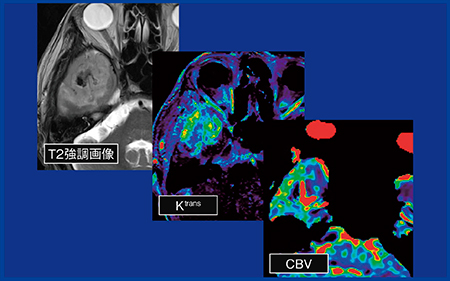

症例2(図2)は,出血を伴う造影病変があり,拡散制限も認められ,不均一な出血と壊死を伴っていることから,形態診断ではglioblastoma(神経膠芽腫)であると考えられた。しかし,perfusion MRIではCBVの上昇はなく,Ktransをはじめpermeabilityはおおむね高値であった。出血や壊死はリンパ腫ではまれであり鑑別が困難であったが,permeabilityの傾向から最終的にはリンパ腫であると考えられた。本症例は実際にCNSLと診断され,permeabilityが非常に有用であった一例である。

図2 症例2:CNSL